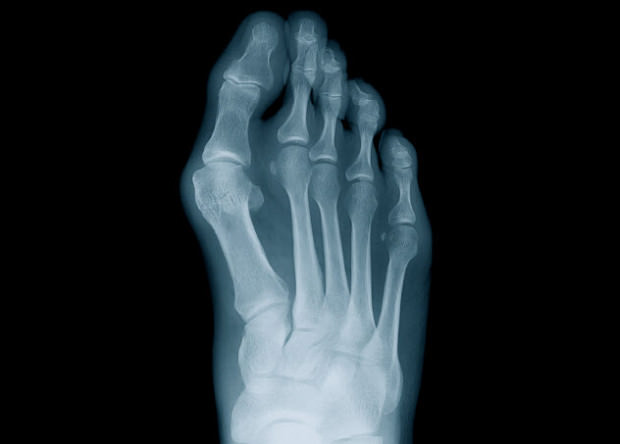

Risk Factors for Bunions and Bunionettes Bunions don’t appear out of thin air. Some bunion-burdened feet were stressed or overworked, and some were just genetically unfortunate. You don’t have to go about your days with uncertainty about your susceptibility to bunions – if you know your risk factor, you can be aware and preventative. And […]